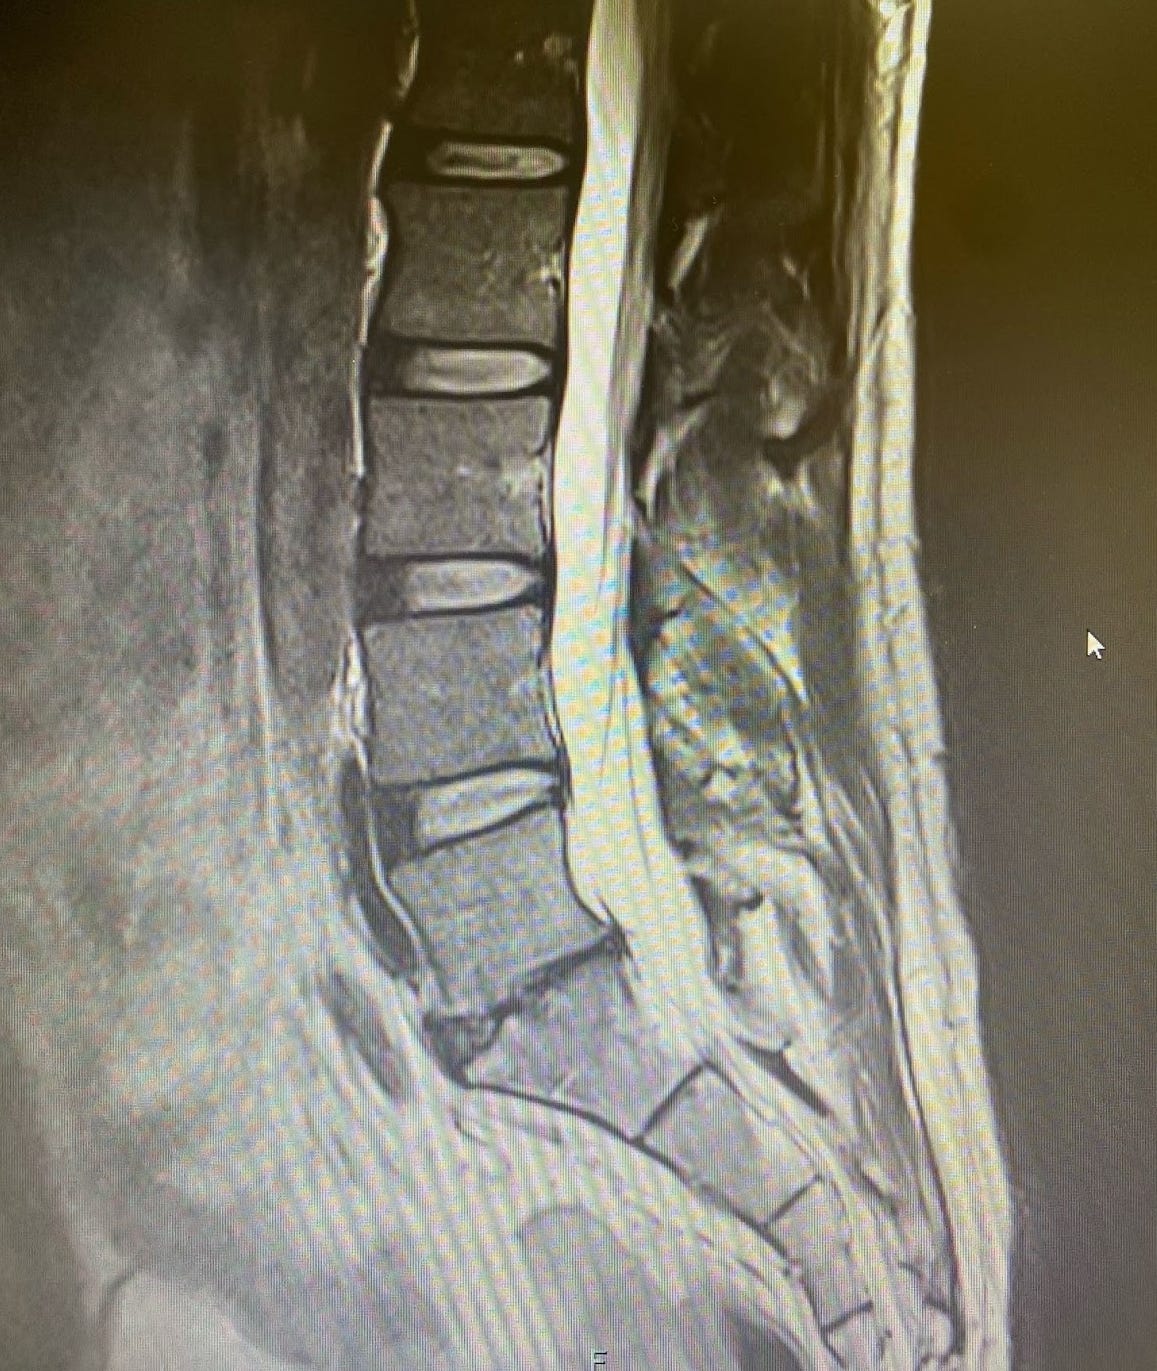

After nearly a year, however, I finally conceded and got an MRI. You don't need to be a radiologist to see something is wrong in the image below; as my five-year-old niece at the time put it, "that looks bad." My L5/S1 disc was essentially non-existent. What likely happened is that for years, I had small tears in the annular ring of my disc until one day it simply gave out. While there are many theories about the pathophysiology of this process, and we still lack a strong consensus on why or how it happens in most people, that was my reality.